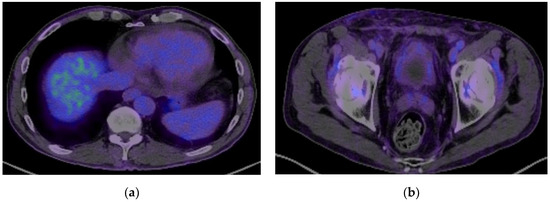

2. Case Presentation